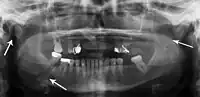

Panoramic radiograph of a simple mandible fracture of the right mandibular body, minimally displaced. Note that the teeth to the left of the fracture do not touch- lateral oblique image demonstrating a fractured mandible.